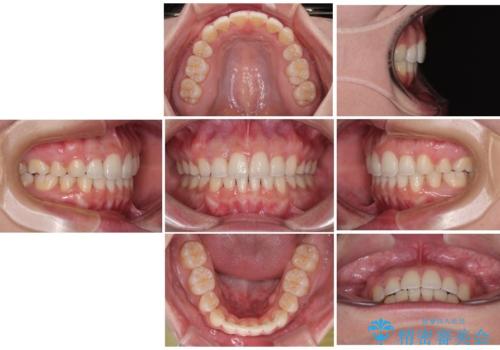

- 全体的なデコボコと口元の突出感を改善したいとのことで来院された患者様です。

このままデコボコを整えるとさらに突出感が増すため、上下左右の第一小臼歯を抜歯し、ワイヤー装置にて矯正しました。

結婚式で途中装置を外した時期がありましたが、2年で治療を終えることができました。